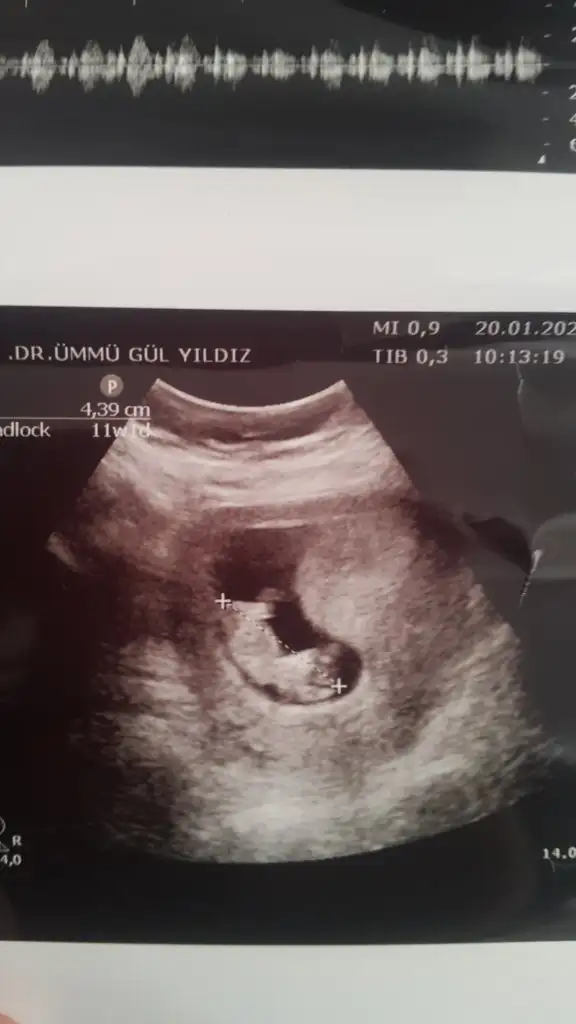

Net degil usg 11+ yada 12+ oldugunda paylaşın yada net varsa usg paylaşın

Screenshot_20200120-154357.webp

mrhaba lütfen yorumlarmisiniz sizce kızmı erkekmi bi arkadas icin soruyorum

Sevgili İkra,

Yorumlarsan çok sevinirim. ☺️❤️